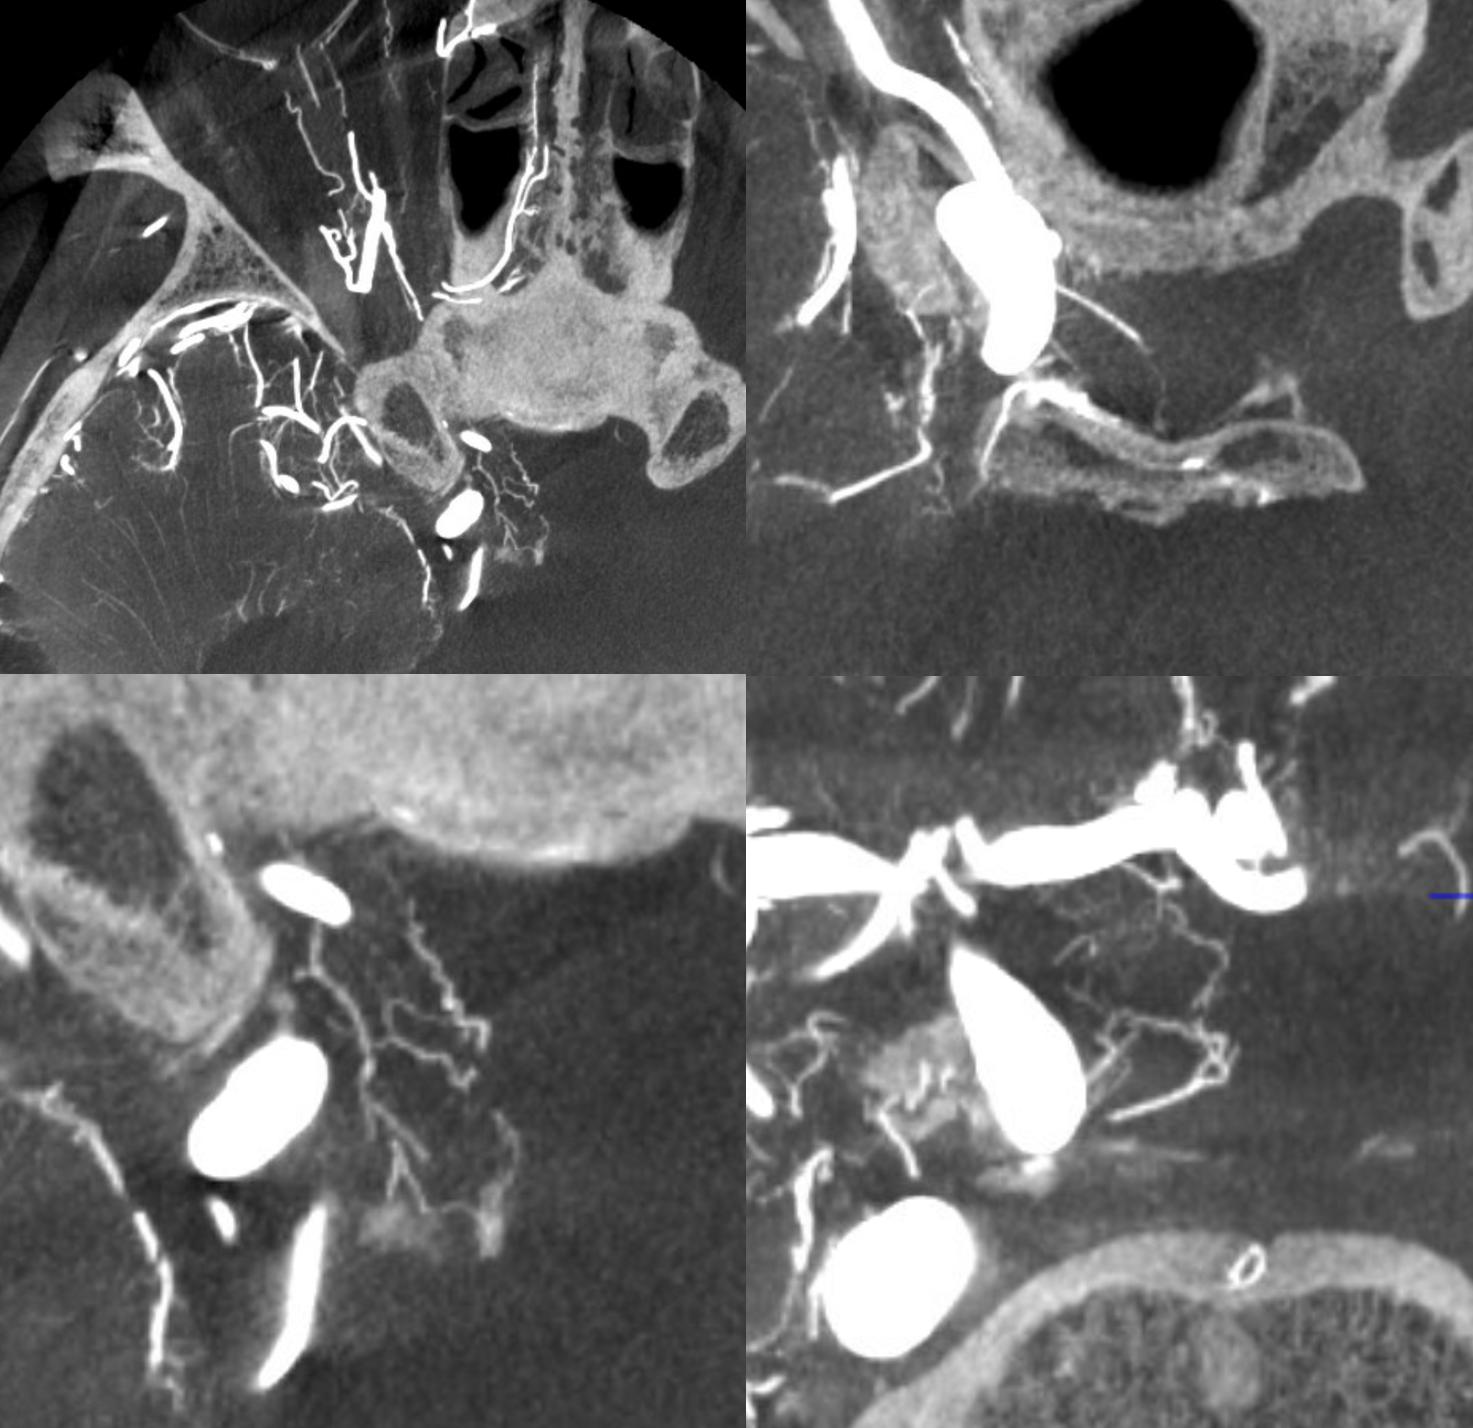

Capsular Arteries of McConnell

These are different from Superior Hypophyseals, but often come up together. This is because they were described by McConnell in a fantastic manuscript on arterial supply to the hypophysis. The anterior hypophysis is supplied by the aforementioned superior hypophyseals. Posterior by the inferior hypophyseals. The arteries of McConnell supply the dura and bone of the sella turcica. They are considered dural, and do not as a rule supply the hypophysis. Too small for even HR CBCT resolution, they are found in about 1/3 to 1/2 of surgical dissections. Origin is from the MEDIAL aspect of the horizontal cavernous segment (opposite side of ILT). Courses medially towards the bottom of the sella. Below (arrows) is a particularly large one (because it feeds some posterior pituitary for some reason). Note beautiful anterior pituitary / stalk supply on bottom right image.

Without arrows: